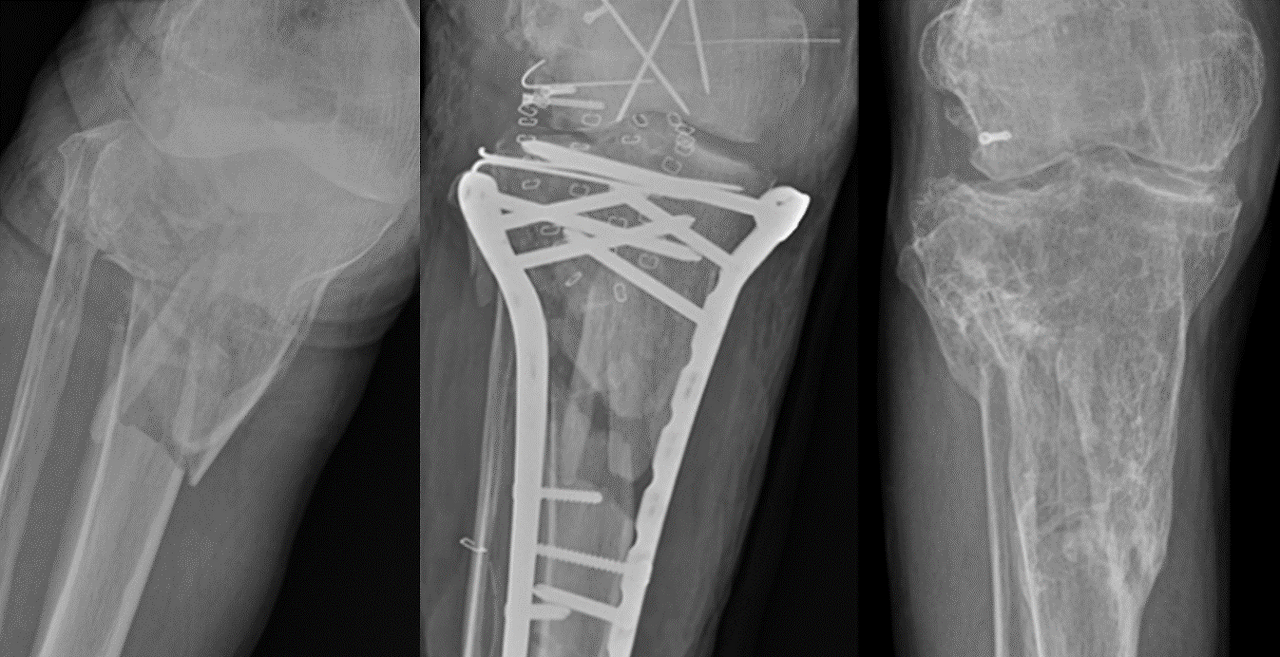

임플란트 제거 여부는 여러 요인을 고려해 신중히 결정해야 합니다. 제거가 필요한 경우로는 재료가 체내를 관통하거나, 부식 위험, 알레르기 반응, 뼈 위축, 암 발생 가능성(매우 드묾) 등이 있습니다. 성장기 어린이나 재료 파손, 감염, 괴사 등의 합병증 발생 시에도 제거를 고려합니다. (그림 2) 아래 예시 그림은 제가 제 1저자로 SCI급 논문에 출판했던 논문에서 발췌한 사진이고, 슬관절과 외상수술의 대가이신 영남대학교병원 정형외과 손욱진 교수님 수술케이스 입니다.☺︎ (Ryu et al., International Orthopaedics, 2019)

그림 2. 수술 전, 후, 금속제거술 후의 영상. 제가 1 저자로 SCI급 저널에 출판했던 논문 사진입니다. ☺︎ (Ryu et al., Int. Orthop., 2019)